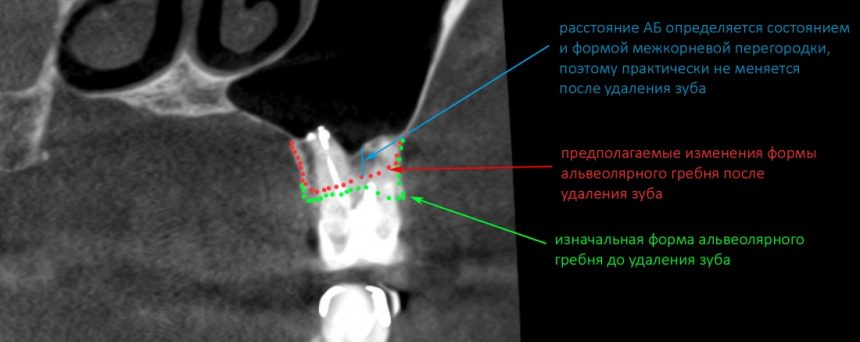

Простой синуслифтинг. Часть I.